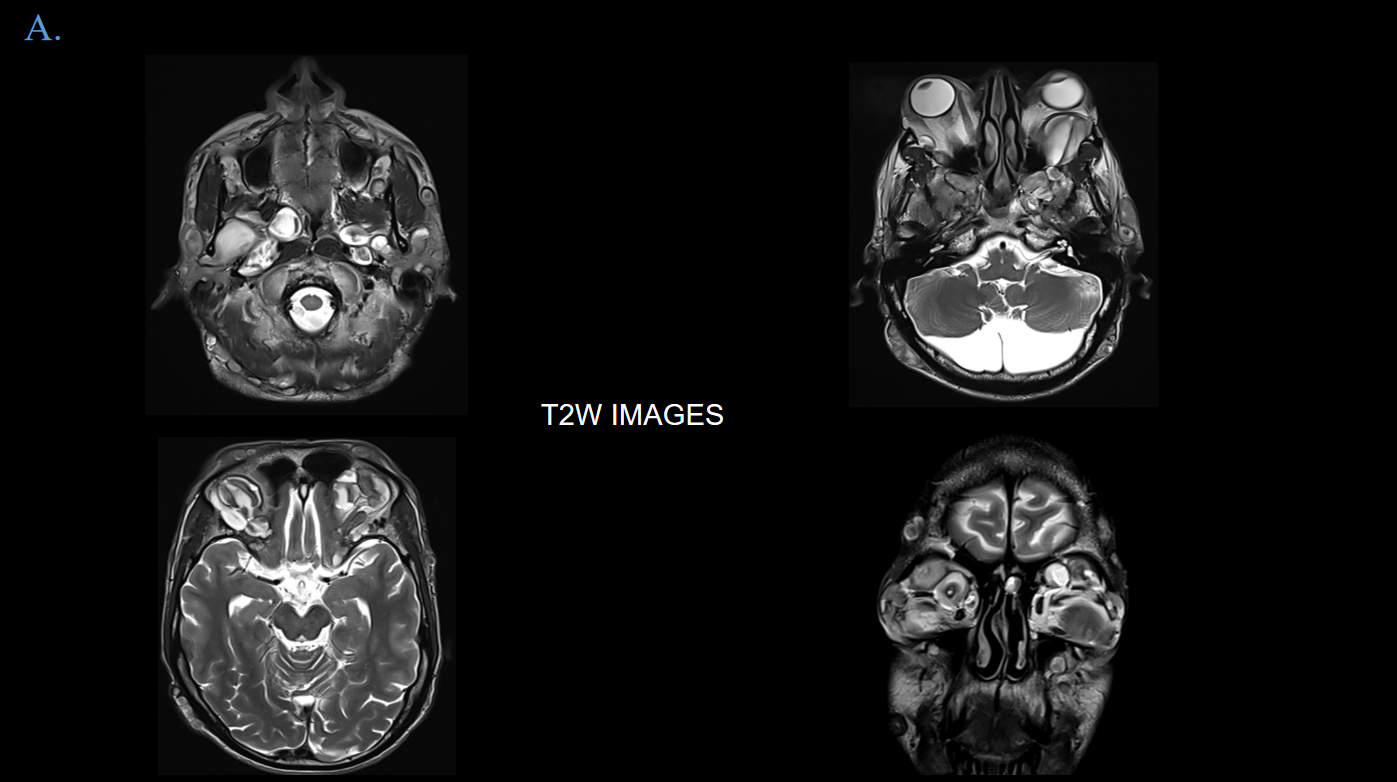

45 year old female presents with complaints of headache, giddiness and occasional vertigo for which MRI Brain was advised.